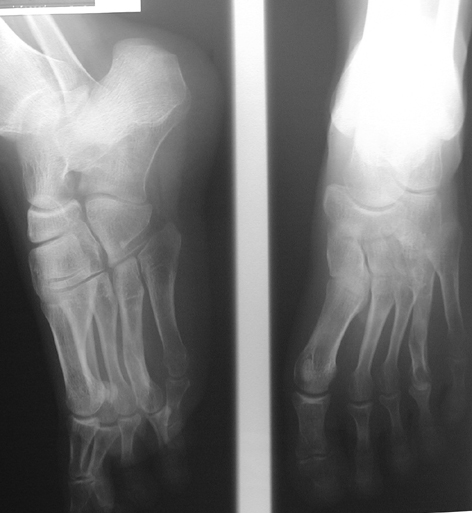

El parmağı (metakarp) ve ayak parmağı (metatars) kısalıkları doğuştan tek başına, geniş bir sendrom grubuyla birlikte, travma sonrası, Freiberg hastalığı (avasküler nekroz) sonrası görülebilir.

Doğuştan metakarp ve metatars kısalığının görülme sıklığı 1/1000’den azdır. Kadınlarda erkeklere göre 5 kat daha fazla görülür ve sıklıkla (%72) iki taraflıdır. En sık 4. parmak tutulur. Bu tür olgularda sorunun nedeni tam olarak bilinmemekle brlikte deformitenin genellikle epifiz plağının erken kapanmasından kaynaklandığı düşünülmektedir.

Metakarp kısalığında kozmetik görünümün bozulması ve dominant elin kullanımı sırasında yorulma, metatars kısalığında ise kozmetik haricinde metatarsalji, kısa parmağın dorsale kayması sonucu deformite oluşması, plantar yönde açılanması sonucu ağrı ve bası ülserleri, ve ayakkabı giymede zorluk nedeniyle ameliyat gerekebilir.

Doğuştan metakarp ve metatars kısalıklarının redavisi için pek çok teknik tanımlanmakla birlikte en çok akut uzatma sonrası kemik uçlarına greft konması ve distraksiyon osteogenezi (kallotasis) kullanılmaktadır. 1 cm.den daha fazla uzatma gereken olgularda kallotasis yöntemi önerilmektedir. Kliniğimizde de metatars ve metakarp uzatma için unilateral eksternal fiksatör ve sirküler eksternal fiksatör yardımıyla distraksiyon osteogenezi yöntemi tercih edilmektedir.